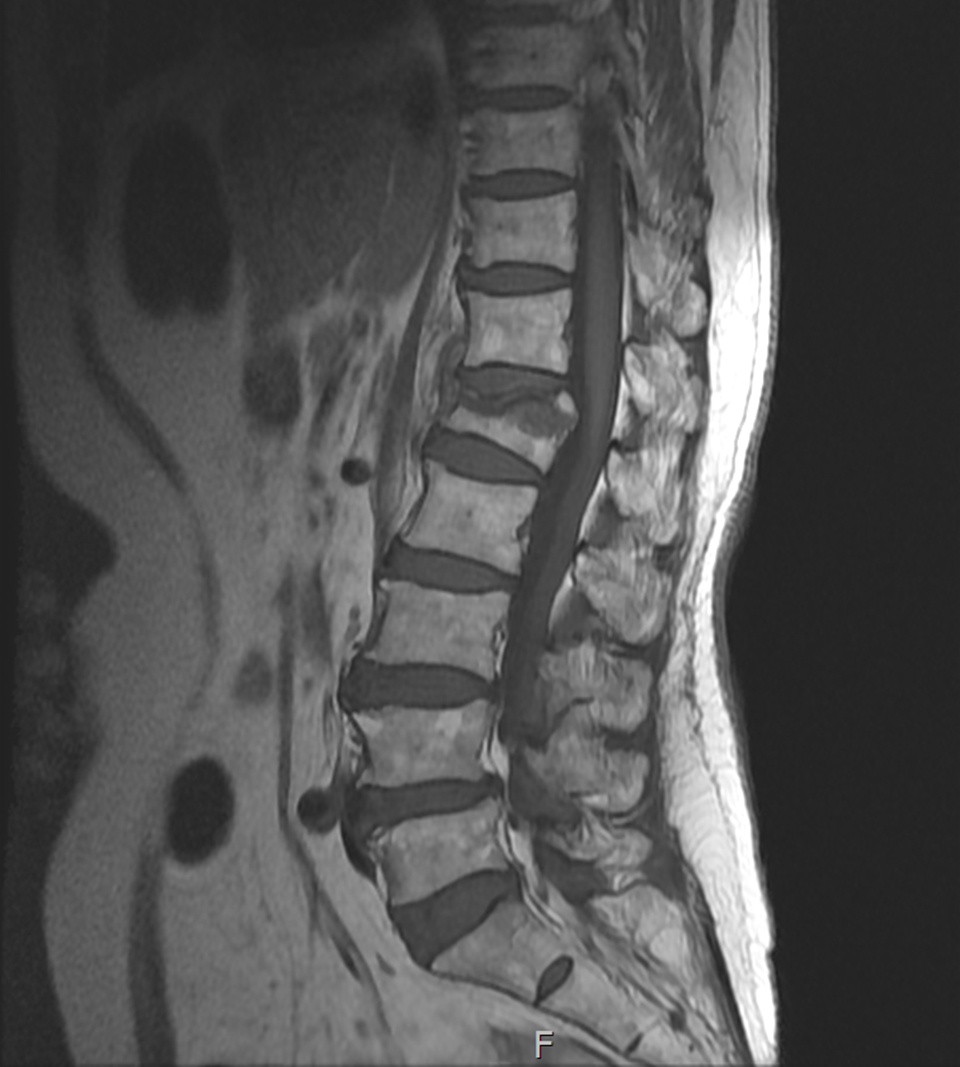

Compression Fracture

<수술전>

- 환자 동의하에 게시된 이미지입니다.